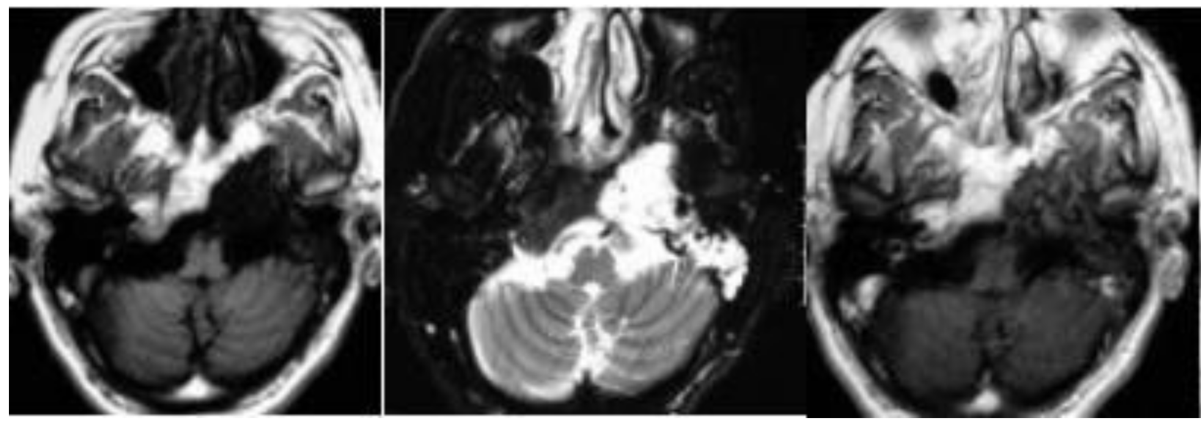

患者40+岁,女性,患者临床症状明显,近1年多来相继头痛、复视、肢体无力、吞咽困难等,当地医院诊断为较大斜坡脑膜瘤,辗转多地医院均告知肿瘤无法全切,术后并发症风险发生率高,后慕名咨询德国国际神经科学中心INI寻求巴特朗菲手术治疗,肿瘤切除97%以上,无相关手术并发症。

术前MR示:斜坡较大脑膜瘤,压迫脑干、颅神经,侵犯基底动脉等

术后MR显示:肿瘤近全切除,术后未见脑血肿、脑水肿,神经血管、脑干等组织保护完好。